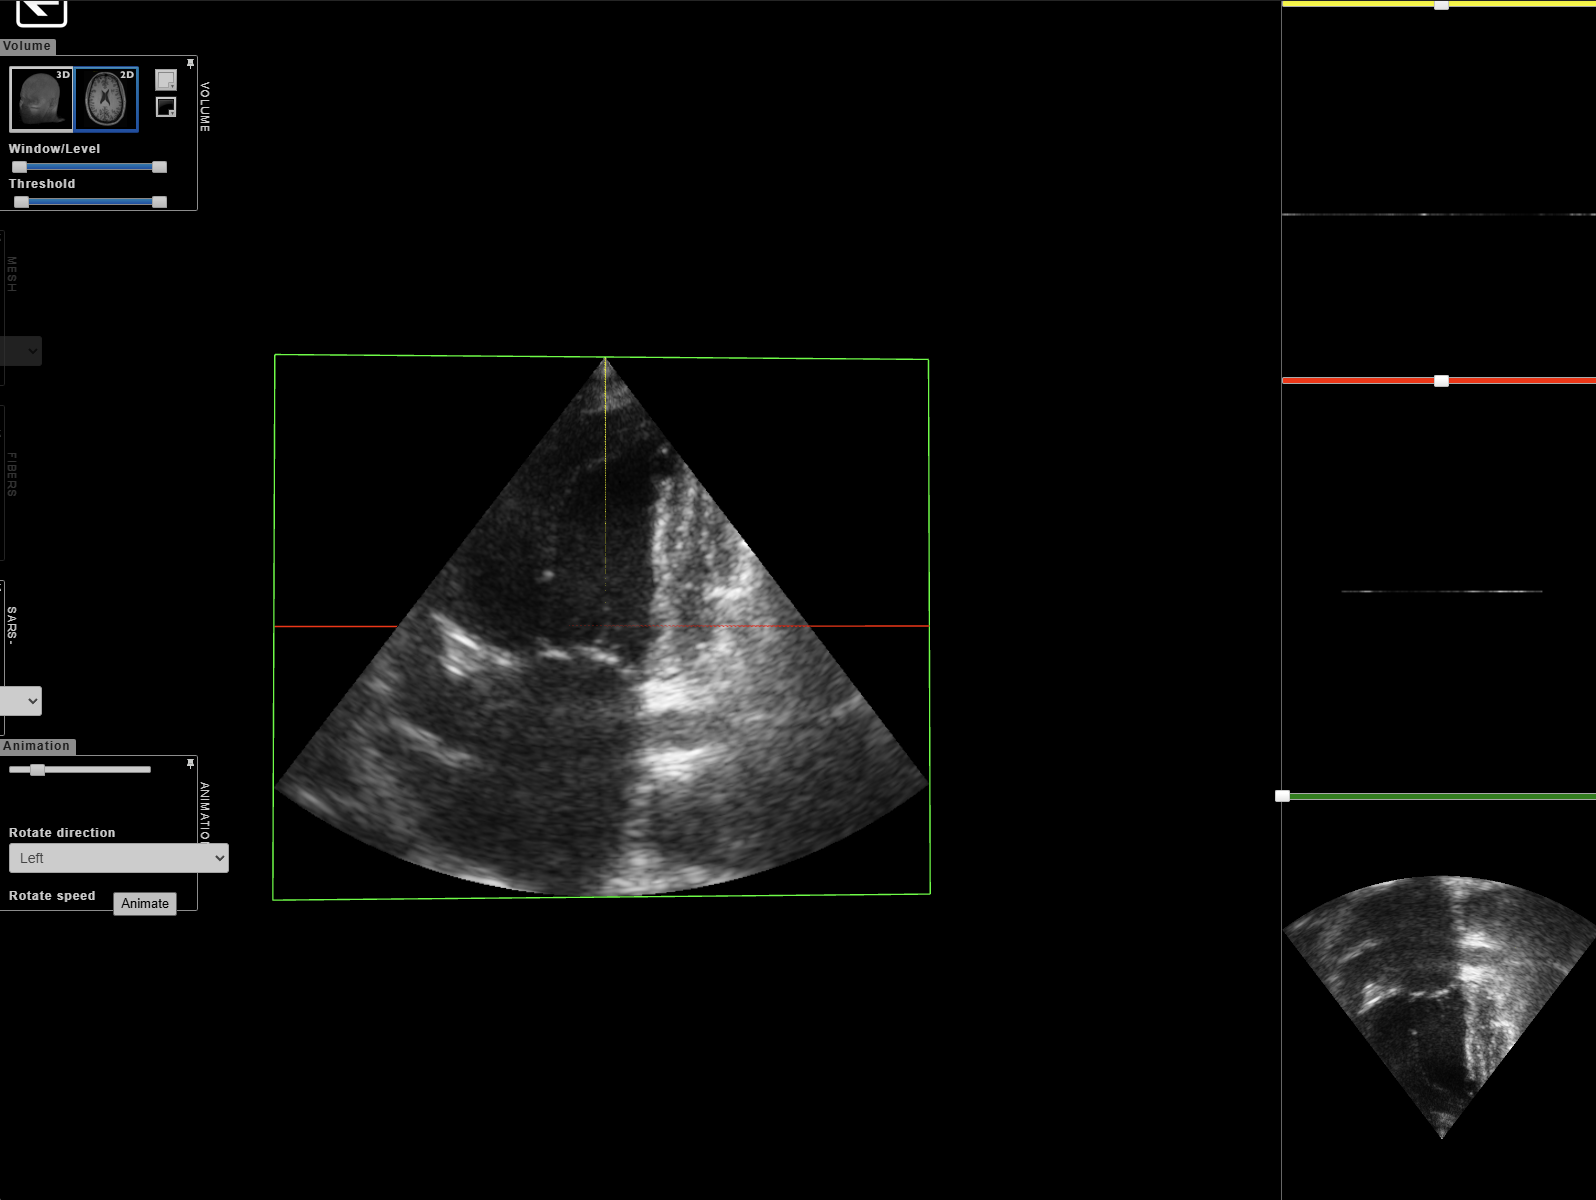

本文将介绍一种利用深度学习中的扩散模型(DDPM),根据心脏解剖结构图“凭空”生成高质量超声影像的算法路径。该方案不仅解决了数据短缺问题,其生成的“Mock影像”质量之高,直接让分割模型的准确率(Dice Score)提升了近 14%。

- 输入(Schema): 一张语义标签图(Label Map)。图中用不同的颜色块标注了左心室、左心房和心肌的位置。

- 处理逻辑: 扩散模型接收这个解剖结构作为“草图”,在去噪的过程中,强制要求 AI 在特定的颜色块区域填充对应的超声波纹理(如灰白色的斑点、瓣膜的阴影等)。

- 输出: 一张解剖结构完全对齐、视觉效果极其逼真的超声影像。